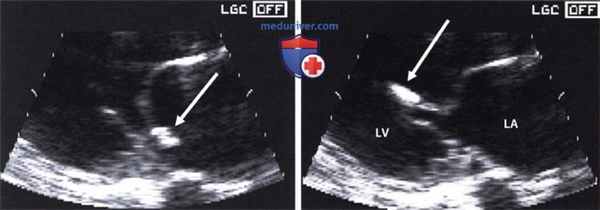

Несмотря на принимаемые меры лечения, состояние пациентки оставалось тяжелым, на фоне кардиогенного шока отмечались признаки острого почечного повреждения (скорость клубочковой фильтрации составила 17 мл/мин/1,73 м 2 ), острой энцефалопатии. По данным трансторакальной эхокардиографии (ЭхоКГ) сердца (табл. 1) на фоне акинеза среднего и апикального сегментов межжелудочковой перегородки, передней и боковой стенок левого желудочка (ЛЖ) с захватом верхушки ЛЖ, отмечалась сепарация листков перикарда в диастолу — 1,2 см за задней и боковой стенками ЛЖ, у верхушки — 0,8 см за счет наружного разрыва миокарда. Вся полость перикарда заполнена отложениями фибрина умеренной эхогенности. В области верхушки со стороны полости ЛЖ лоцировался дополнительный эхосигнал (пристеночный тромб) размером 2,7х1,6 см, под которым визуализировалось эхонегативное пространство размером 1,6х0,9 см (место разрыва миокарда) (рис. 4, 5). Кровоток через место разрыва миокарда не определялся.

Рис. 4. Трансторакальная ЭхоКГ пациентки Б.

Примечание: апикальная 2-х камерная позиция: сепарация листков перикарда в диастолу — 1,2 см за задней и боковой стенками ЛЖ, у верхушки — 0,8 см за счет наружного разрыва миокарда, под ним эхонегативное пространство размером 1,6х0,9 см (место разрыва миокарда).

Сокращение: ЛЖ — левый желудочек.

Рис. 5. Трансторакальная ЭхоКГ пациентки Б.

Примечание: парастернальная позиция ЛЖ по короткой оси: полость перикарда заполнена отложениями фибрина умеренной эхогенности. В области верхушки ЛЖ лоцируется дополнительный эхосигнал (пристеночный тромб).